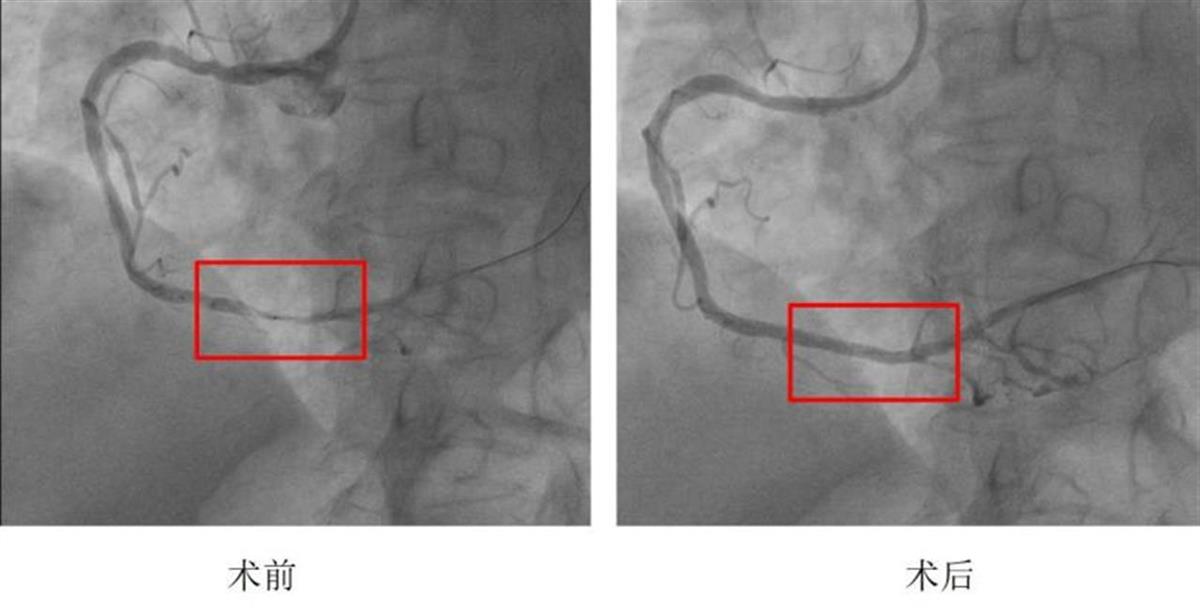

患者被从门诊直接转运到心脏介入导管室后,高血压病科吕永楠教授和方钊医生迅速为其实施PCI手术。造影显示:右冠脉远段像“被掐住的橡皮管”,远段血流几乎中断。术中,专家团队仅用15分钟就成功植入一枚药物洗脱支架打通“生命通道”。当血流重新灌注心肌的瞬间,监护仪上心电图原先抬高的ST段应声回落,医护人员和焦急守候在导管室外的家属同时长舒了一口气。